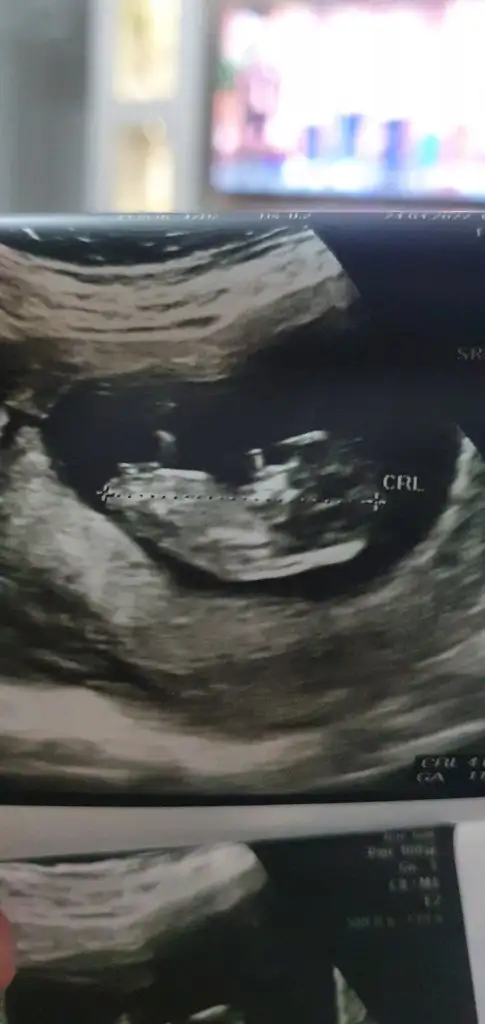

Merhaba benimde ikizlerime bakar mısınız biri 11+4 biri 11+2günlük resimde

• 83A7A9EB-371B-45BE-B16B-1A2A573EE617.webp

18,4 KB · Görüntüleme: 57